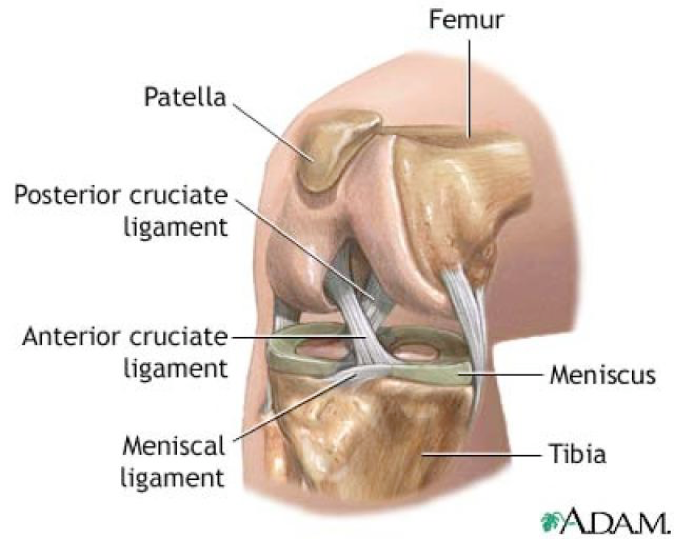

Анатомические изображения менисков и коленного сустава

Раздел: Иллюстрированные советы